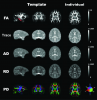

Infant Macaque MRI And DTI Templates

Infant Macaque MRI And DTI Templates Images

3 Images available.

Description:MRI (T1-w) template (by ANTS)